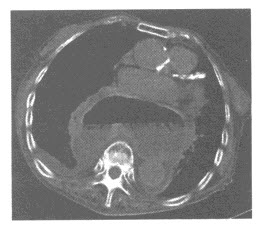

37、多项选择题

男,53岁,无痛性血尿2个月余,CT扫描如图示,下列说法正确的是()

A.右侧输尿管下段可见沿输尿管走行的软组织肿块影

B.软组织肿块边缘毛糙不平

C.其上方的输尿管扩张

D.考虑为输尿管移行细胞癌

E.考虑为输尿管内血块